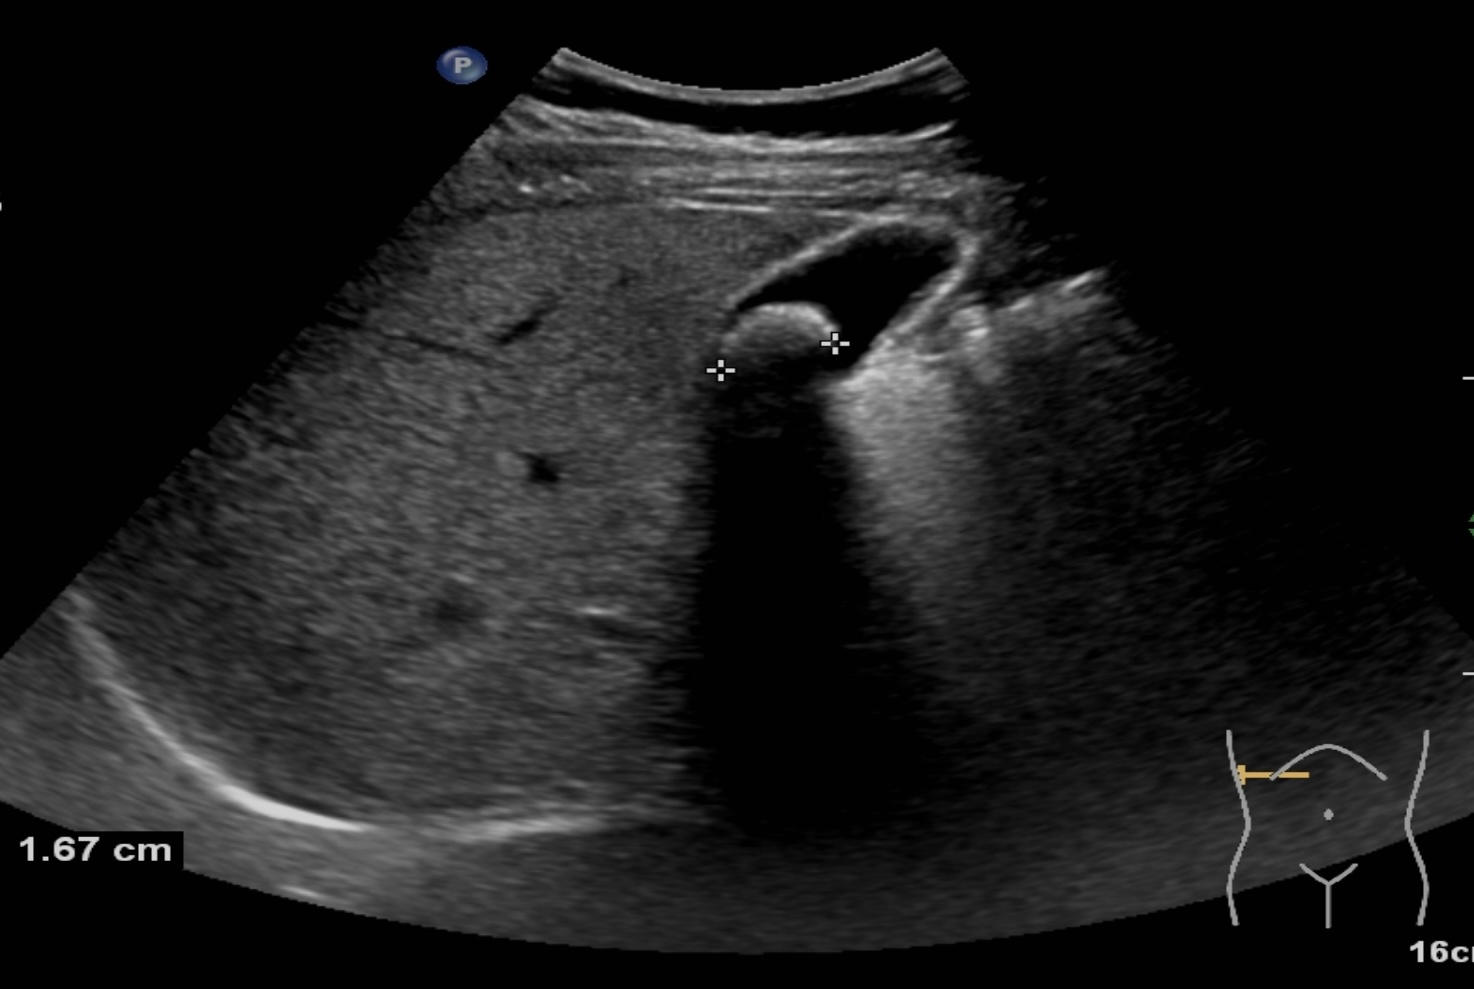

膽結(jié)石診斷方式很多,包括彩超、CT、核磁共振、膽管造影等方式都可以對(duì)膽道結(jié)石進(jìn)行診斷,但是彩超具有無創(chuàng)、無痛、無輻射、廉價(jià)、快速、可重復(fù)性強(qiáng)等優(yōu)點(diǎn),在臨床上被廣泛應(yīng)用作為膽結(jié)石的首選診斷方式。注意做肝膽彩超檢查必須要空腹,才能準(zhǔn)確檢查出膽道結(jié)石哦!

膽囊結(jié)石超聲圖像 | |